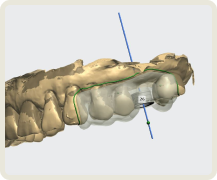

이제는 임플란트 회사, 임플란트 브랜드 선택의 관점에서 벗어나서 임플란트 수술 진단부터 최종 치아 제작까지. 이 모든 과정에서 보철학적 목표를 디지털 방식으로 어떻게 완성해 내는지가 선택의 관점이 되어야 합니다.

이로운 치과는 간단하고 정확하며 안전한 치료를 위한 디지털 진료 방식을 지향합니다.

개인 맟춤 디지털 수술 가이드

이 모든 술식, 장비, 소프트웨어 노하우가 집약된

이로운치과의 디지털 임플란트